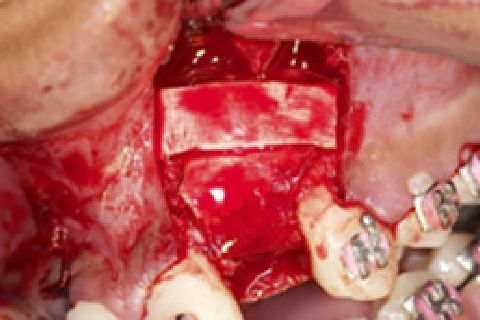

''Neste caso, a paciente gostaria de melhorar a estética do seu sorriso, prejudicada pela agenesia de ambos os incisivos laterais superiores. Devido à baixa disponibilidade óssea, observada na tomografia computadorizada, optou-se pela instalação de implantes estreitos (Xive – Dentsply Implants – 3.0 mm de diâmetro) com regeneração simultânea (Biooss e Biogide – Geistlich), ao invés de realizar enxerto ósseo prévio. Após osseointegração, foi realizado condicionamento gengival com provisórios e novo enceramento diagnóstico. O caso foi finalizado com coroas livres de metal sobre os implantes e microlaminados cerâmicos sobre os incisivos centrais (e.max - dissilicato de lítio – Ivoclar Vivadent), visando o mínimo desgaste de estrutura dental sadia. ''